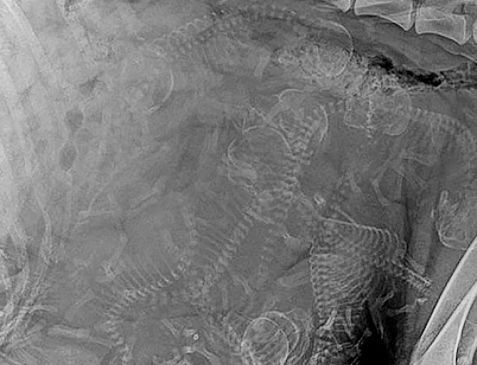

Desde su descubrimiento en 1895 por parte del profesor alemán Wilhelm Röntgen los rayos X han jugado un papel fundamental en las sociedades humanas. Son usados en campos tan distintos como el sanitario, la seguridad en el transporte e incluso la identificación de obras de arte. Su utilización está tan extendida que a veces deja imágenes tan curiosas como las recogidas en esta galería.